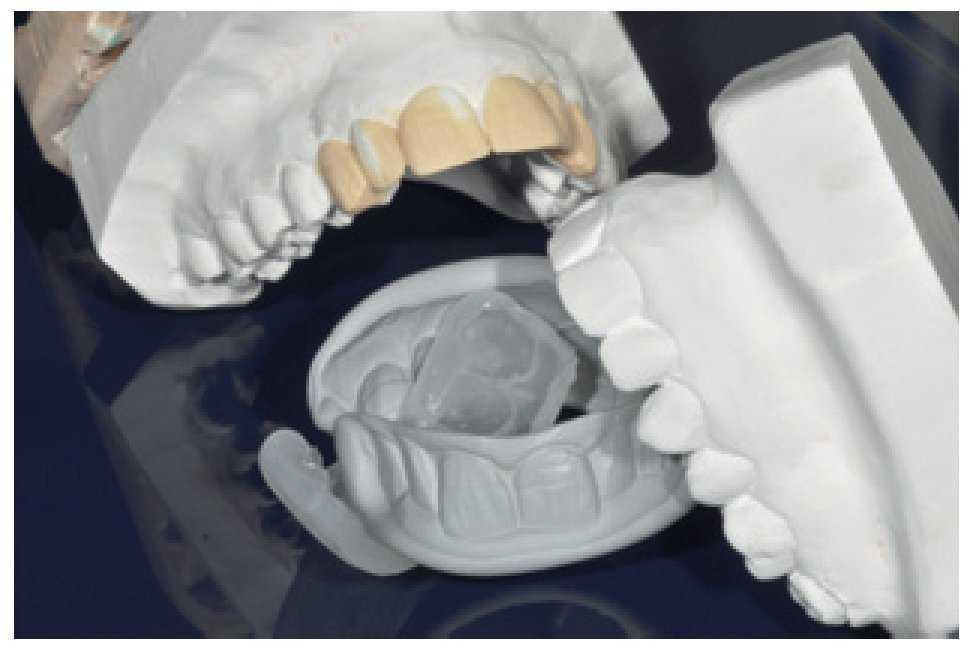

Sólo en este punto se empezó a estudiar la forma de los dientes, y el primer paso consistió en pedirle a la paciente que nos proporcionara fotografías tomadas antes de recibir sus restauraciones. Se realizó un encerado diagnóstico sobre modelos de escayola extradura (figura 35). Estos modelos de escayola fueron usados para fabricar en el laboratorio una serie de llaves de silicona pesada de soporte palatino, seccionándolas en dirección sagital y vestibulopalatina. Estas guías son indispensables para establecer las paredes palatinas y controlar el grosor del composite durante la técnica de estratificación, así como para ejercer de matriz para la forma final de las restauraciones.

Figura 35 Llave de silicona fabricada en el laboratorio a partir del encerado.